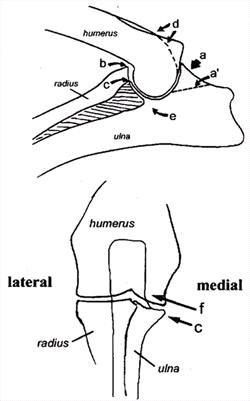

| The Canine Elbow |

| The Canine Elbow

a) Anconeal process, site of osteophyte development

a') Line of separation for UAP

b) Site of osteophyte development

c) Medial coronoid process

d) Site of osteophyte development

e) Trochlear notch

f) Site of osteochondrosis lesion |